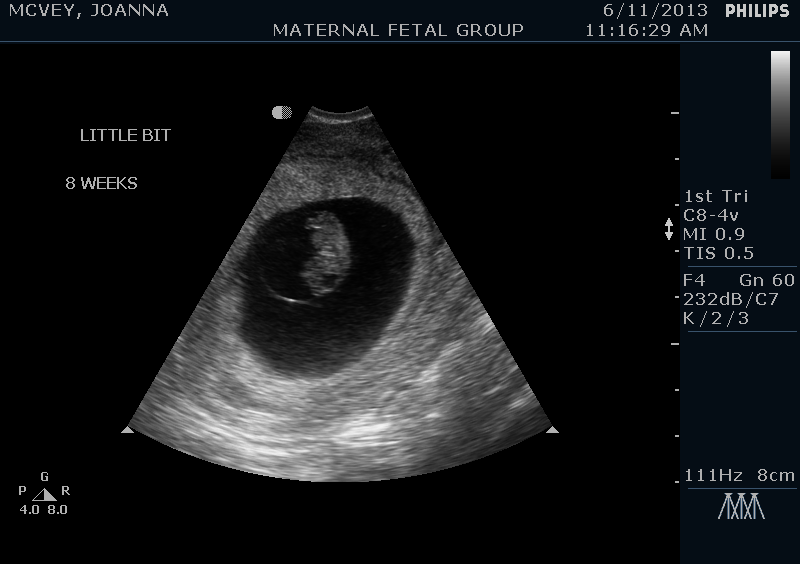

This baby is due January 21st, and we’ve already had our first doctor’s appointment and seen our little peanut via ultrasound.  At first I was positive this baby would be another boy, but since I’ve been SO sick this time around (much more than I was with Grayson), now I’m wondering if this one is a girl.  I guess only time will tell!

Here’s a couple pictures of our little munchkin.